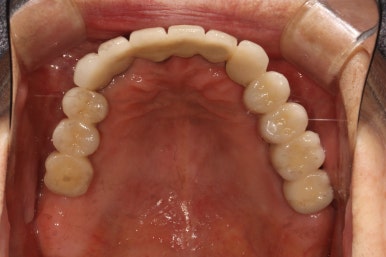

생각보다 임시치아보다 훨씬 매끈한 표면과 비슷한 색깔을 자랑하는 지르코니아 크라운입니다.

오스템 원가이드 네비게이션 임플란트 시스템을 이용하면, 정교하게 이상적인 위치에 임플란트를 심어낼 수 있어 자연스러운 임플란트 보철물을 제작하는데 많은 도움을 받을 수 있습니다!!

최종 완성된 보철물은 상당히 이상적인 형태를 갖고 있습니다.

차이를 별로 못느끼실 수 있겠지만, 임플란트 보철물 완성 6개월 후 방문 때 구강내 사진입니다.

감사히도 환자분께서 상당히 깨끗하게 유지하고 계셔서, 잇몸에 염증하나 없이 너~무 보기 좋더라구요.

임플란트도 6개월에 한 번씩 스케일링을 받으셔야 합니다.

치아랑 똑같이 치태도 쌓이고 치석도 생긴답니다.

결국은 자연치아의 만성치주염에 해당하는 임플란트주위염으로 발전할 수 있기 떄문에, 자가 관리를 확실히 그리고 철저하게 하시는 것이 매우 중요해요!!!